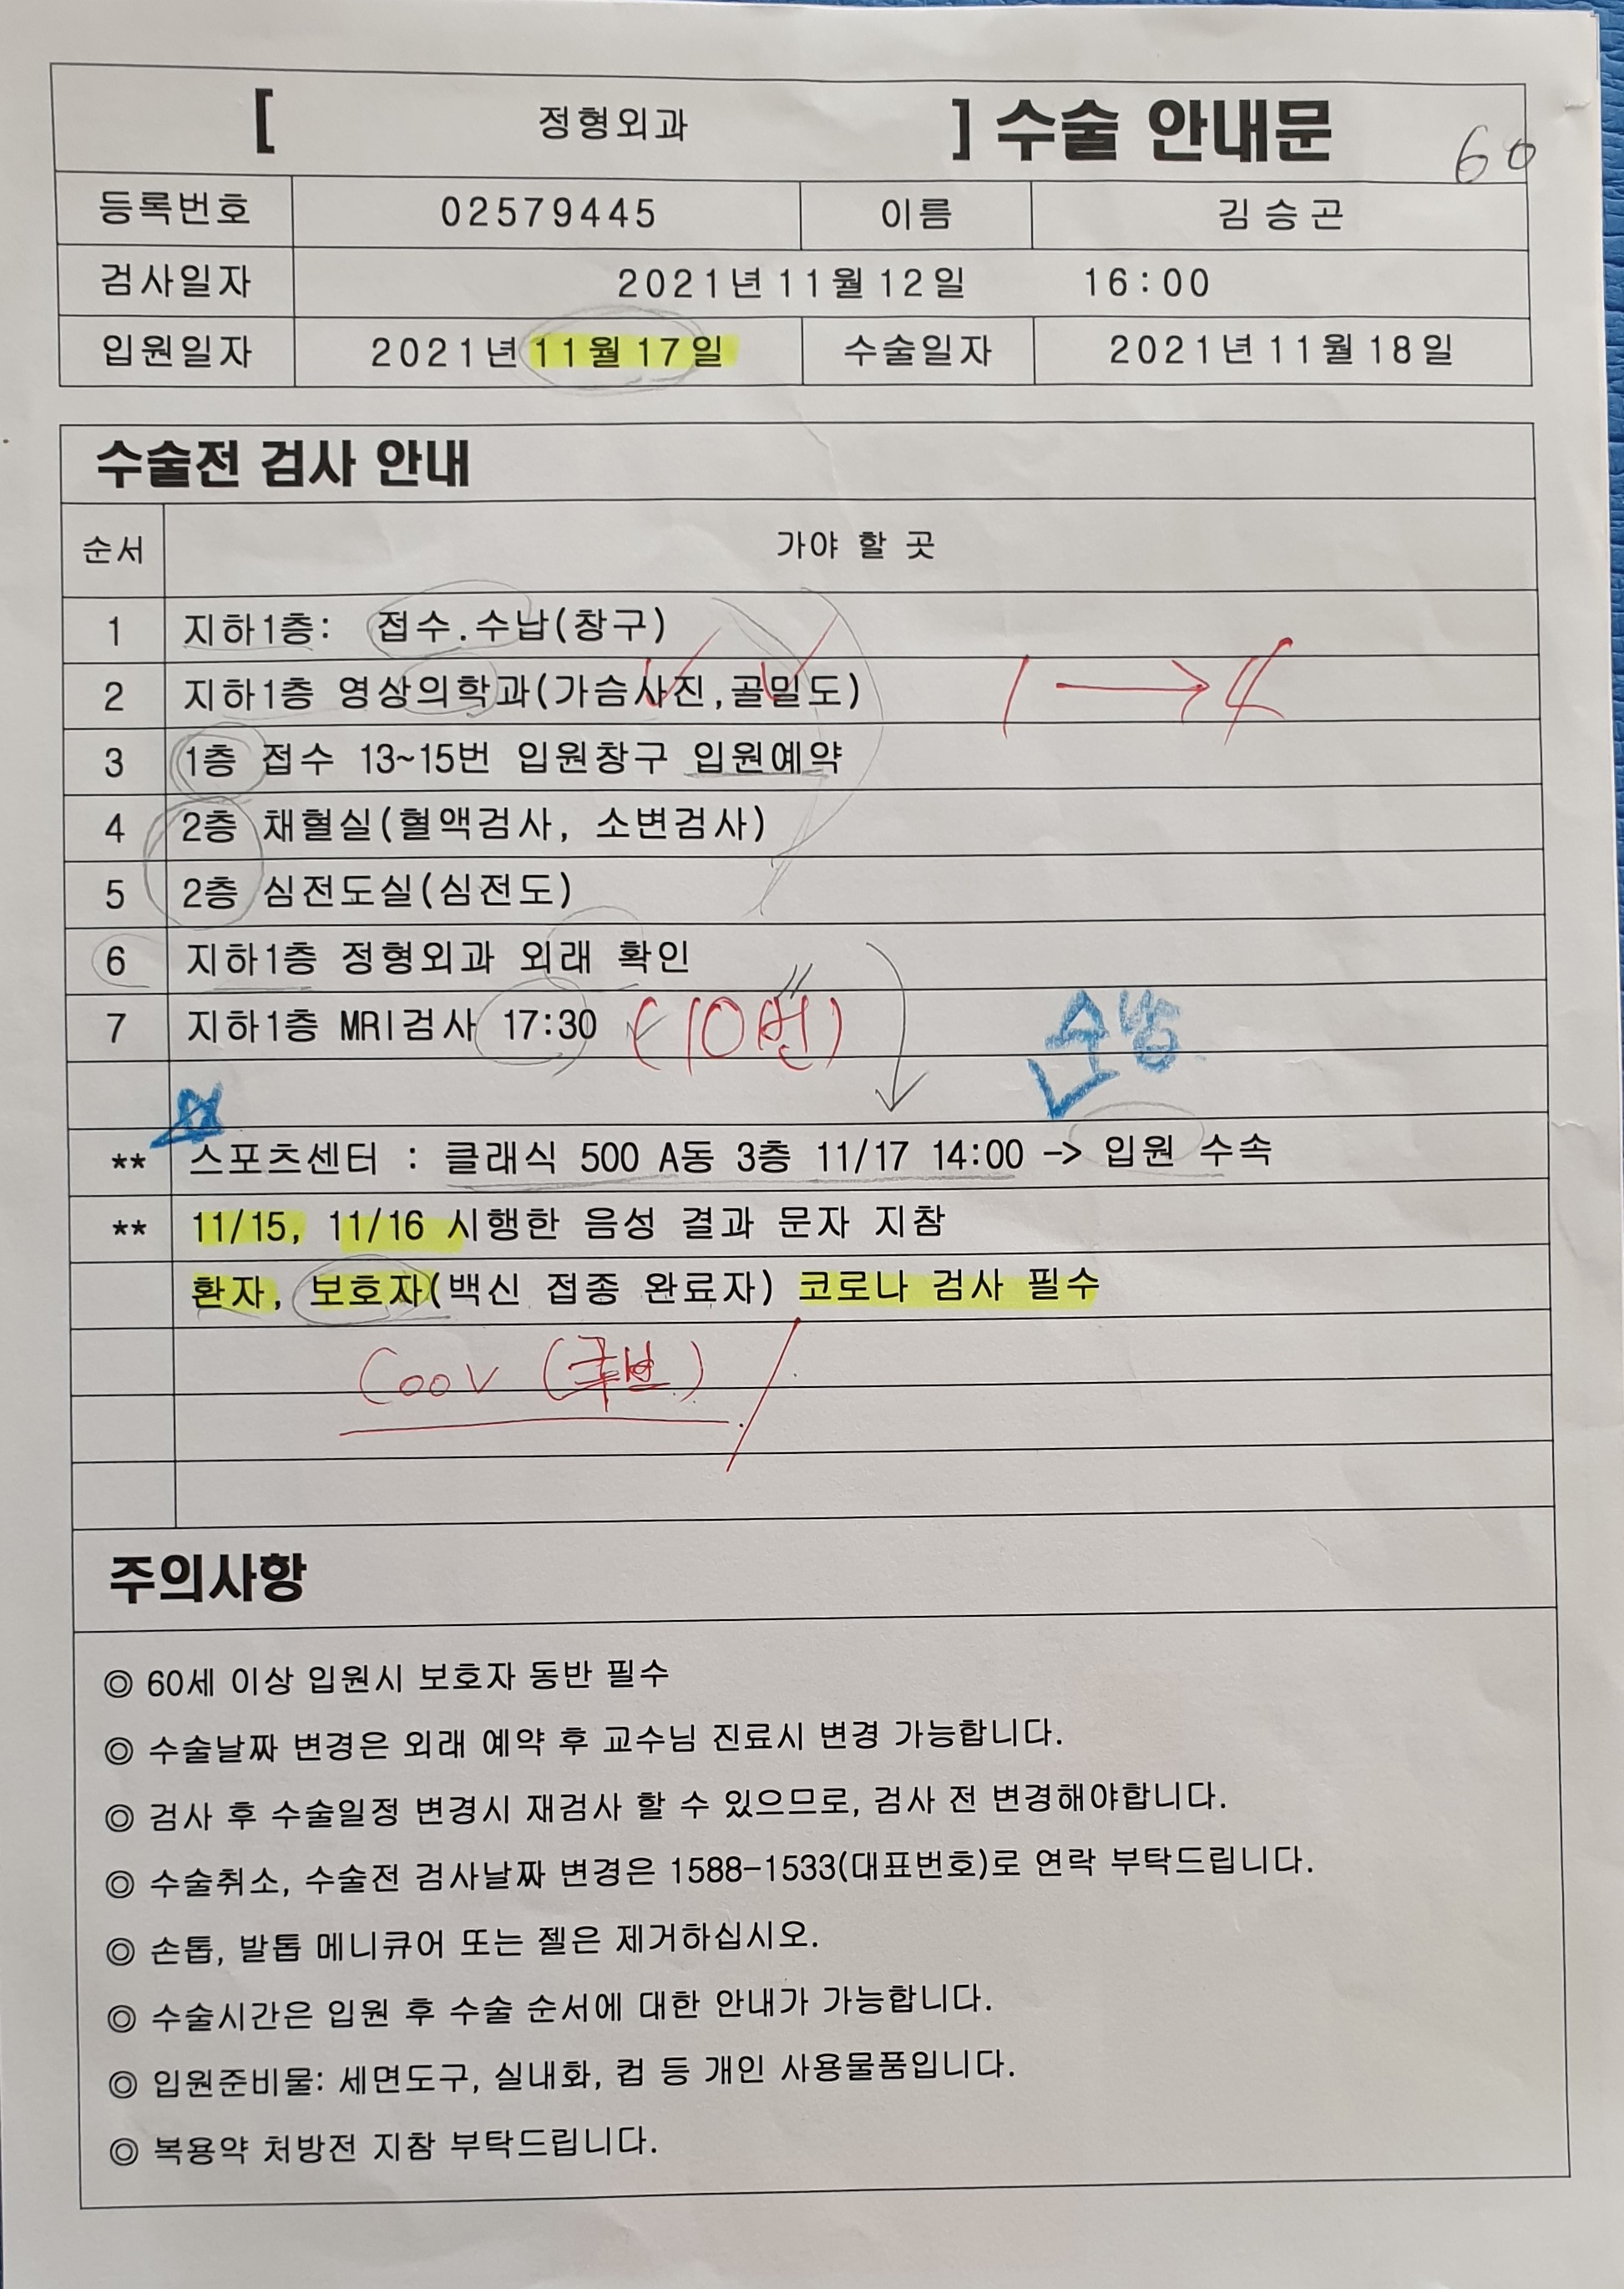

또 수술전 검사를 12일 하자고...

그러면서 수술전 진료일은 없다며 수납후 검사를 받으면 된다 한다.

11월 12일.............

16시까지 와서 수납후 검사를 받으라는 통보에 아마도 도착이 15시 30분쯤 되었지 싶다.

수납하는데 1,262,650원이다.

영상의학과에서 가슴사진과 골밀도 사진을

그리고 수납옆 창구에서 입원 예약을

또 채혈실에서 채혈및 소변 검사를

그리고 심전도 검사

영상의학과에서 17시 30분 예약 되어 있는 MRI검사를....

11월 12일 수술 사전검사 수납

11월 12일 영상의학과

11월 12일 채혈실

11월 12일 MRI검사